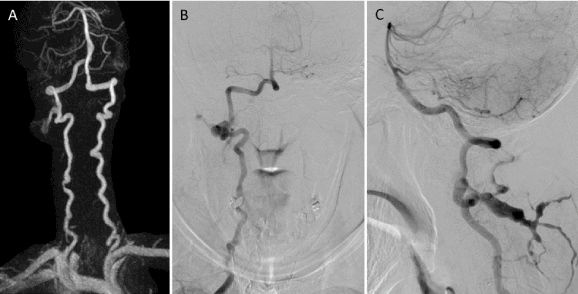

A 58- year-old man with a medical history of hypertension, diabetes mellitus, and dyslipidemia, was admitted to the local hospital due to sudden onset of vertigo, ataxia, and diplopia. Previous medication included amlodipine 10 mg, metformin 500 mg, and simvastatin 20 mg once daily. There was no history of trauma. Computed tomography (CT) scan and magnetic resonance imaging (MRI) of the brain obtained the same day showed multiple infarctions in right cerebellum and cerebellar peduncle (Figure 1). Clopidogrel 75 mg once daily was given to him. With fully recovery, he was discharged home one week later. After first attack, the patient suffered from another 7 episodes of stroke in the last 3 years before transferring to our institute. Every episode, he was brought to multiple hospitals, and obtained CT, MRI, and/or magnetic resonance angiography (MRA) of the brain and neck. All hospitals reported cerebral infarction in posterior circulation territory without occlusion of extracranial and intracranial vessels. Despite changing different types of antiplatelet or even trying to give double antiplatelet together with strict control of stroke risk factors was attempted during this period, episodes of acute neurological deficit still occurred. Finally, recurrent ischemic stroke had prevented with clopidogrel 75 mg and aspirin 325 mg once daily. Serologic evaluation, thrombophilia screen or coagulation studies (i.e., protein C, protein S, antithrombin III, anticardiolipin antibodies), duplex ultrasonography of carotid and vertebral arteries, electrocardiography including 24-hour Holter monitoring, and transthoracic echocardiography were done which all showed unremarkable to explain the cause of frequent recurrent cerebral infarctions. Following multiple recurrent stroke, the patient developed aggravating neurological symptoms, including ptosis, dysarthria, dysphagia, right hemiparesis, right arm numbness, and the worst quadriparesis. These problems likely occurred together and some of them resolved almost completely in a few weeks to a month. Few months before transferring, his daughter noticed that the patient gradually developed cognitive decline and was unable to remember people’s names, places and often lost the way in his house. Sometimes he reported visual hallucinations. Furthermore, she also noticed that his speaking is rather slower than usual. His activities of daily living had deteriorated and need partial support.

Figure 1. Magnetic resonance imaging (MRI) of the brain obtained after initial onset. Sequential images of axial fluid-attenuated inversion recovery (FLAIR) MRI at the level of pons (A), cerebellar peduncle (B), and medulla (C) shows multiple hyperintensities in the right side of cerebellum, representing of multiple infarctions of the posterior circulation